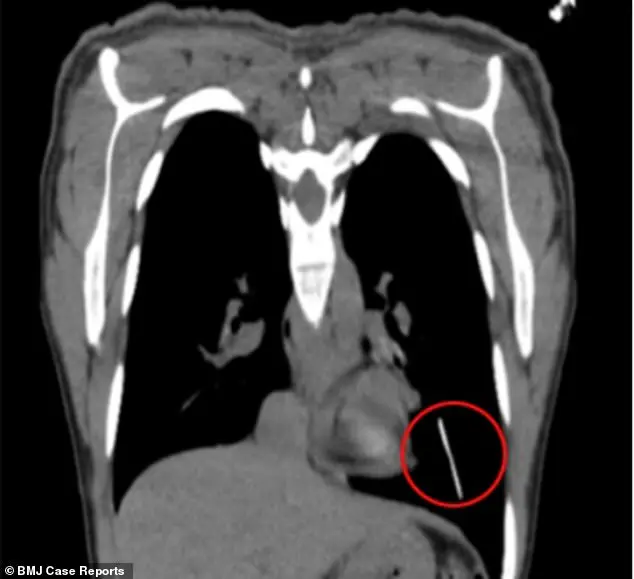

Après l’avoir admise au département gynécologie de l’établissement, les médecins touchent son bras pour sentir son implant – une petite tige rigide – mais ne trouvent rien. Ils font alors passer un scanner à la patiente, qui révèle que l’implant a migré au fond de son poumon gauche.

Comme les auteurs de l’article l’expliquent dans le BMJ Case Reports, il est probable que l’implant soit passé dans le système sanguin de la jeune femme. "Si l’implant est introduit trop profondément, il peut migrer dans le système veineux, puis dans les artères pulmonaires", développent-ils. De plus, une activité physique intense peut augmenter le risque de migration, selon eux. "Le risque est également plus élevé chez les femmes très minces" ajoute la Dre Tania Adib, gynécologue, interrogée par le Daily Mail.